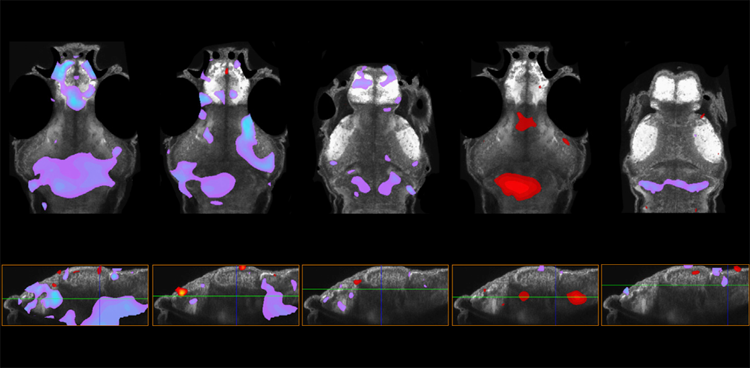

圖1 在五種具有自閉癥相關基因變異的斑馬魚模型中,前腦的大小增加(紫色)或減少(紅色)。